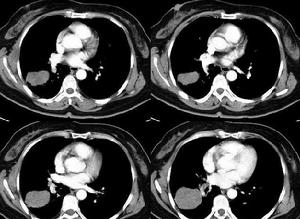

纖維肉瘤治療方案二、採取綜合治療,術前大劑量化療,然後根據腫瘤浸潤範圍作根治性切除瘤段、滅活再植或置入假體的保肢手術,或截肢術,術後繼續大劑量化療。纖維肉瘤肺轉移的發生率極高,除上述治療外,還可行手術切除轉移灶。近年來由於早期診斷和化療迅速發展,纖維肉瘤的5年存活率提高至50%以上。

纖維肉瘤後期會出現轉移,如肺轉移、肝轉移等,當然同時也會伴有相應的纖維肉瘤轉移症狀。如肺轉移患者多會出現咳嗽、痰血、低熱、胸痛、氣悶等,嚴重的話患者會出現面頸部水腫、聲嘶和氣促等症狀。同樣有肝轉移的患者可會出現肝痛、乏力、消瘦、黃疸、腹水等症狀。